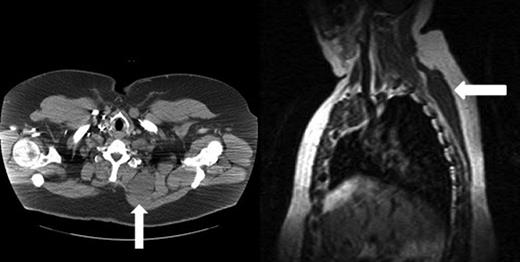

Computed tomography (CT) scan of the chest demonstrated a large cystic mass between the posterior aspect of the thoracic ribs and deep to the muscles of the left back and scapula. There was no obvious connection with the spinal cord or pleural space. No solid or enhancing component was identified.

Chest magnetic resonance imaging delineated a large cystic mass extending from the level of the lower neck to just above the level of the diaphragm measuring 11 cm transversely, 4.5 cm anteroposteriorly and 23 cm craniocaudally (Fig. 1).

(Left) Chest CT scan shows the large cystic mass (arrow) between the left posterior ribs and muscles of the left back and scapula. No solid or enhancing components are identified. (Right) Chest MRI shows the large cystic mass extending from the level of the lower neck to just above the level of the diaphragm.